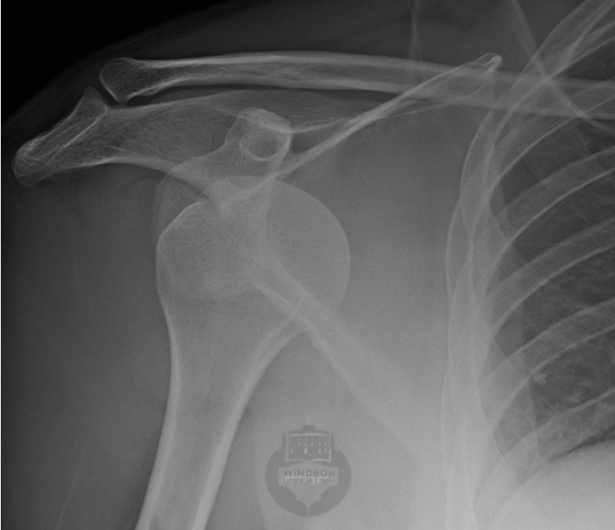

The shoulder is the most mobile joint in your body.  To allow such movement, the ball (humeral head) has to sit in a very shallow socket (glenoid) – a situation that mimics a golf ball balanced on a tee.  (You will know that a golf ball can be easily knocked off a tee!).  Stability of your shoulders therefore relies on intact soft tissue and bony stabilizers and fine co-ordination of the muscles around your shoulder.  Injury, abnormal development or incorrect movement patterns can expose your shoulder to instability.  An unstable shoulder may either come partially out (subluxtion) or totally dislocate.  Approximately 90% of the time, the humeral head dislocates anteriorly.

Sometimes, there is also damage to the bone. This can affect both the socket (Bony Bankart) and/or the humeral head (Hill-Sachs defect).

A Bony Bankart equates to  a chipped golf tee, so your humeral head has less of a platform on which to rest.  This may happen as an acute fracture, or, with several dislocations, you may suffer gradual erosion of the front-lower portion of your socket.

The HIll-Sachs lesion occurs when your dislocated humeral head is resting against the sharp front edge of your socket.  The humeral head bone is softer, so it gets a dent in its posterior surface.   If you have a large Hill-Sachs, this can cause your humeral head to slide out of joint as you rotate your arm outwards.

Following reduction of your shoulder; which should be confirmed on x-rays; you will need to rest your shoulder, take painkillers and anti-inflammatories and wear a sling.  This will help you recover after your injury